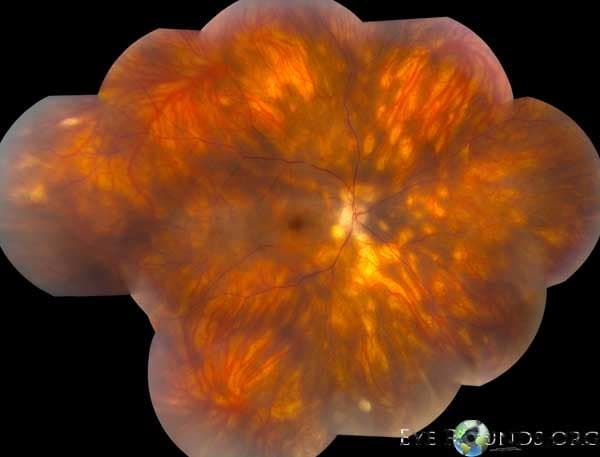

Clinical Images

High-resolution clinical photographs showing various presentations of macular degeneration.